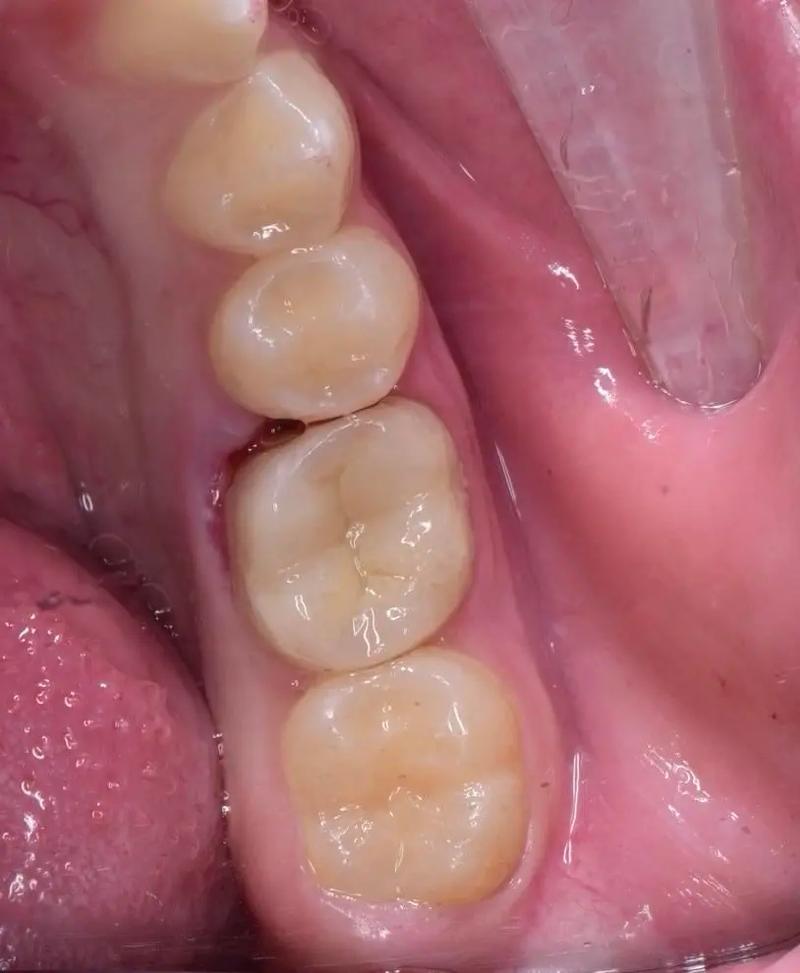

(图片来源网络,侵删)